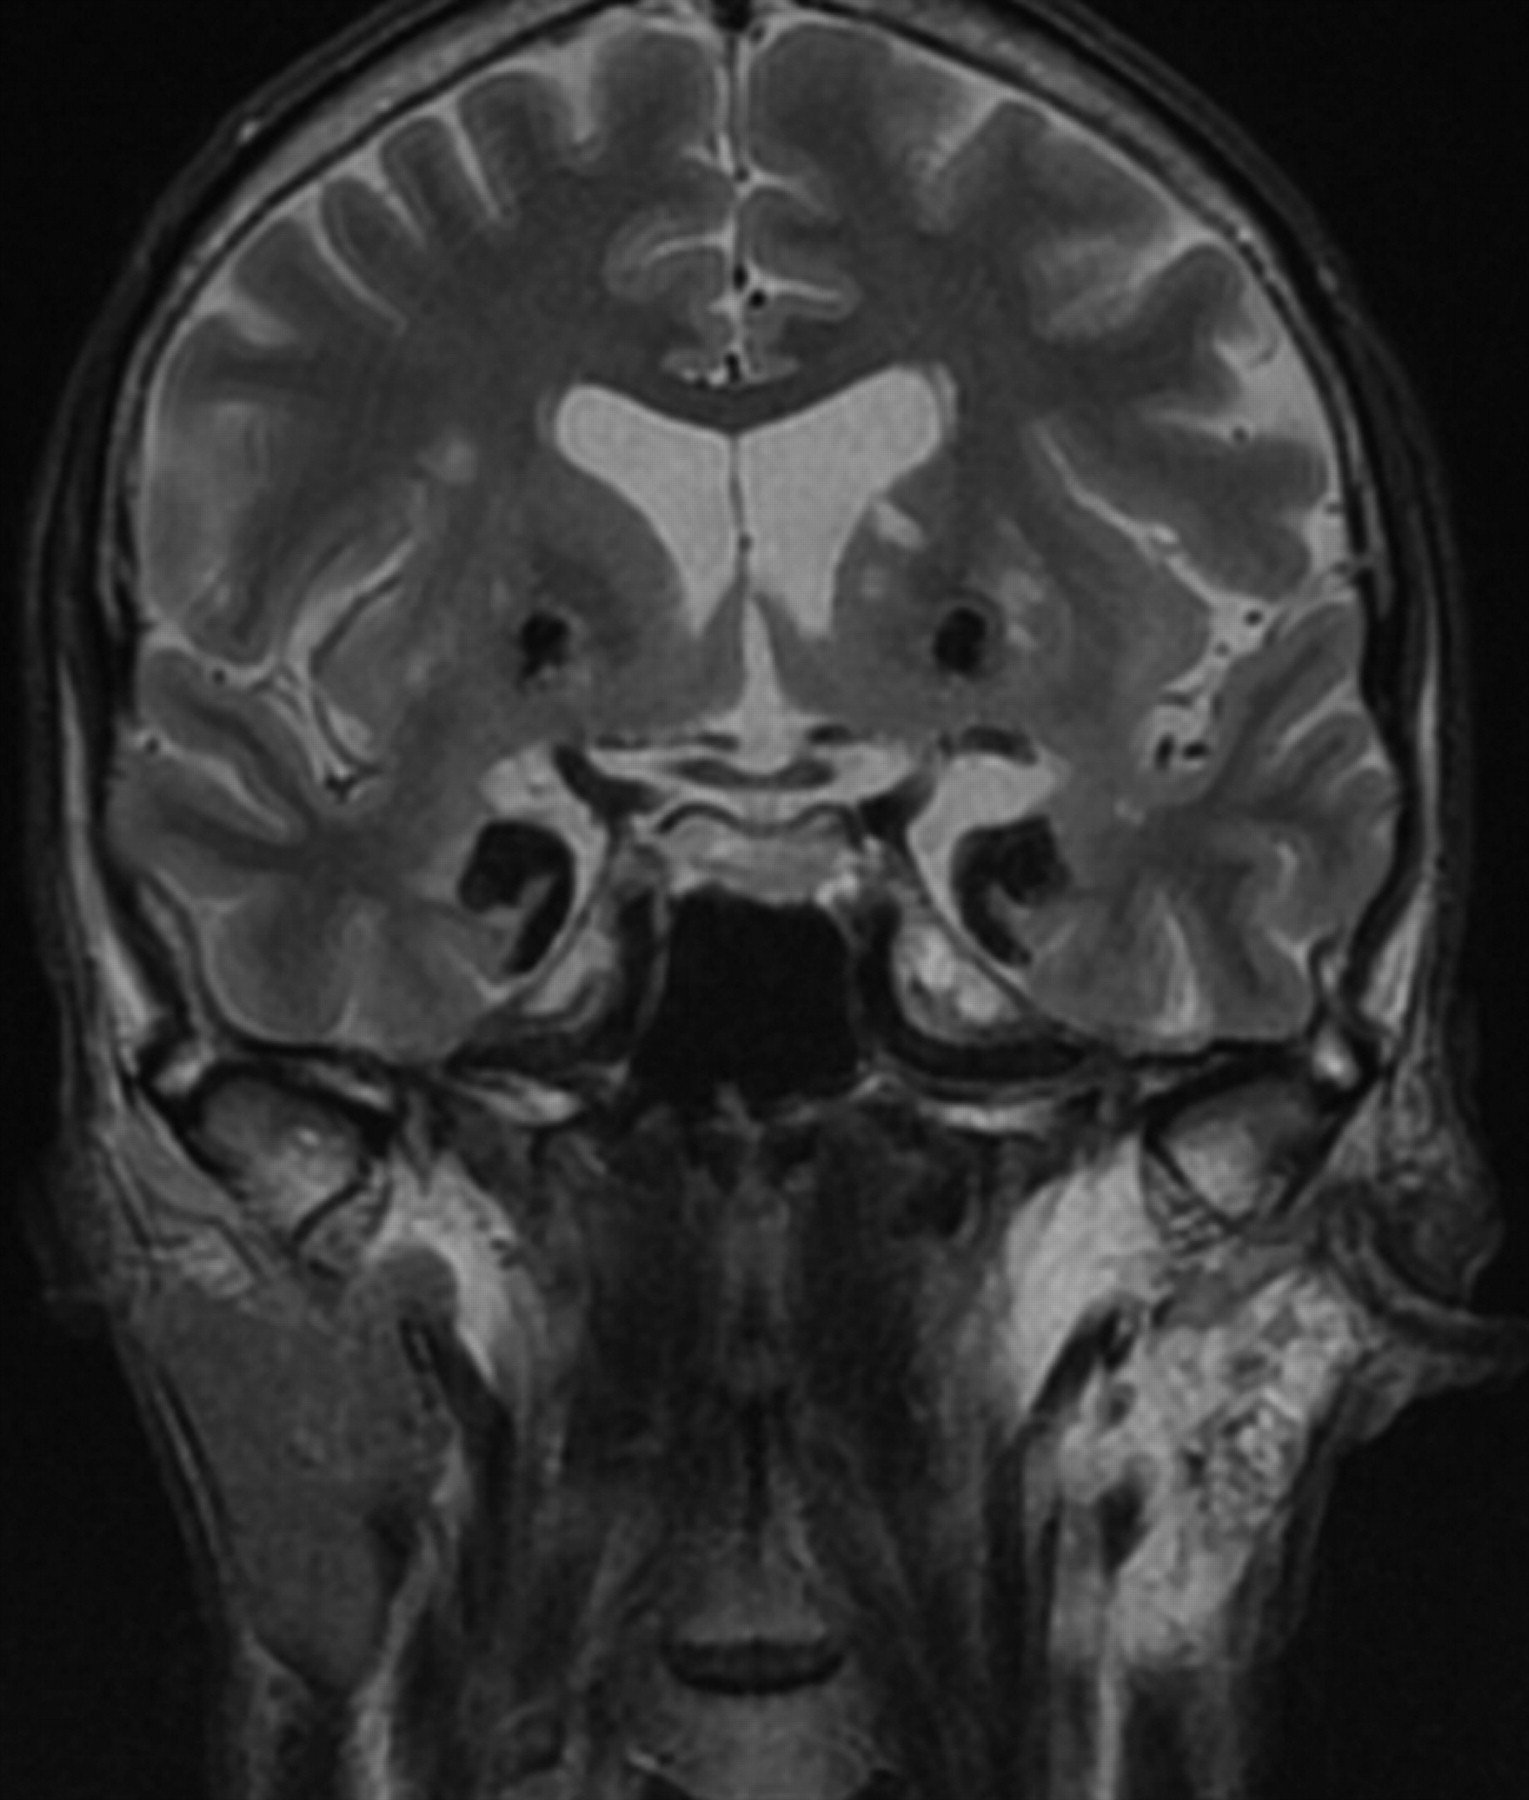

On CT, there were signs of bilateral symmetric amygdaloid and striatum calcifications without mass effect (Fig 2). On T2-weighted images, there were marked hypointense lesions in the mesial temporal lobes immediately anterior to the temporal horns and rounded bilateral striatal lesions (Fig 3). An incidental finding of parotid gland T2 hyperintensity was positively correlated with a history of left parotid gland recurrent inflammation.

Patient 1. Coronal T2-weighted MR imaging (TR, 4500 ms; TE, 90 ms) reveals symmetric bilateral markedly hypointense lesions in the temporal lobes. There is involvement of the amygdaloid bodies, parahippocampal gyrus, and uncus as well as symmetric rounded hypointense lesions in the striatum. Note the left parotid gland hyperintensity representing fatty infiltration from recurrent parotid gland inflammation.